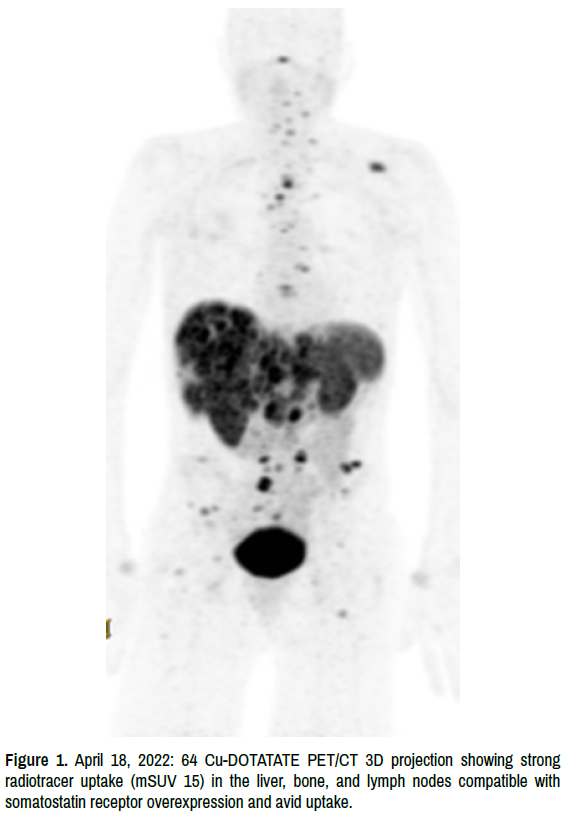

In November 2021, a repeat liver biopsy was performed for consideration of a clinical trial. The pathologic diagnosis based on histomorphology and immunophenotype suggested metastasis from known breast primary carcinoma positive for ER, PR, synaptophysin, chromogranin-A, and GATA- 3. The patient had undergone all standard chemotherapy treatments with no positive outcomes. Disease progression was present throughout all treatment protocols, and hospice was then the recommended standard of care. In January 2022 upon further testing of the November 2021 specimen there showed a strong somatostatin receptor subtype 2 immunohistochemistry (SSTR2 IHC) over expression. This was followed up on April 2022 with a 64 Cu-DOTATATE PET/CT scan, specifically to determine whether a tumor is a somatostatin receptor-expressing and avid neuroendocrine tumor. The test suggested the presence of extensive metastasis, most prominently in the liver with high radiotracer uptake consistent with the findings of a neuroendocrine tumor. Uptake in the liver on this test (max standard uptake value 15) is much more intense than the fluorodeoxyglucose positron emission tomography (FDG PET) scan (max standard uptake 9). Additionally, extensive bone metastasis with intense uptake was observed, with mild adenopathy in the chest and upper abdomen [4] (Figures 1-4).

integrative-oncology-radiotracer

Figure 1. April 18, 2022: 64 Cu-DOTATATE PET/CT 3D projection showing strong radiotracer uptake (mSUV 15) in the liver, bone, and lymph nodes compatible with somatostatin receptor overexpression and avid uptake.